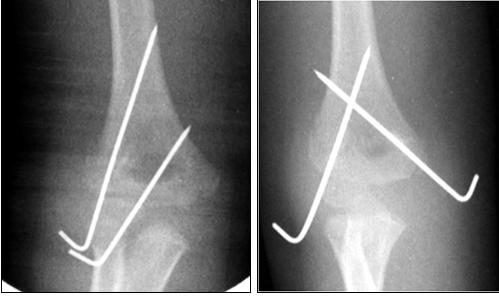

Fratture e distacchi del massiccio condiloideo dell'omero distale - Frattura sovracondiloidea

Nelle fratture composte o modicamente scomposte il trattamento è sempre conservativo con gomitiera gessata e adeguato monitoraggio radiografico.

Nel caso di frattura trasversa, a 2 frammenti, con scarso spostamento dei monconi e nei pazienti più piccoli è indicato tentativo di riduzione incruenta della frattura, previo congruo periodo di trazione su balcanica. Ottenuta la riduzione, la frattura deve essere immobilizzata in apparecchio gessato toraco-brachiale. Nelle fratture scomposte con marcata componente rotatoria è possibile procedere dopo riduzione incruenta alla stabilizzazione con fili di Kirscher percutanei con configurazione incrociata o parallela a seconda del tipo e della sede della frattura.

Nelle fratture con edema/tumefazione marcata del gomito (specie se vi è stata latenza temporale fra il momento del trauma e la presentazione in Pronto Soccorso), nel caso sia presente un deficit neurologico, in caso di insuccesso della manovra riduttiva (per interposizione di tessuto muscolare o periosteo o grave comminuzione della frattura) è indicata la riduzione cruenta con approccio laterale, postero-laterale o posteriore e sintesi mediante fili di Kirschner. In caso di potenziale lesione nervosa del nervo mediano o radiale o dei vasi omerali è necessario utilizzare un approccio antero-laterale con esplorazione chirurgica vascolo-nervosa.

Per l'immobilizzazione post-operatoria è sufficiente una gomitera gessata con bendaggio reggibraccio. Successivamente in base all'evoluzione radiografica (callo di frattura) e alla stabilità dell'eventuale osteo-sintesi si deciderà se iniziare la mobilizzazione del gomito o proseguire con tutela (valva rimovibile o nuovo apparecchio gessato).